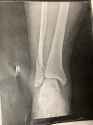

Nyjah skull fracture

https://imgur.com/WzimdLX